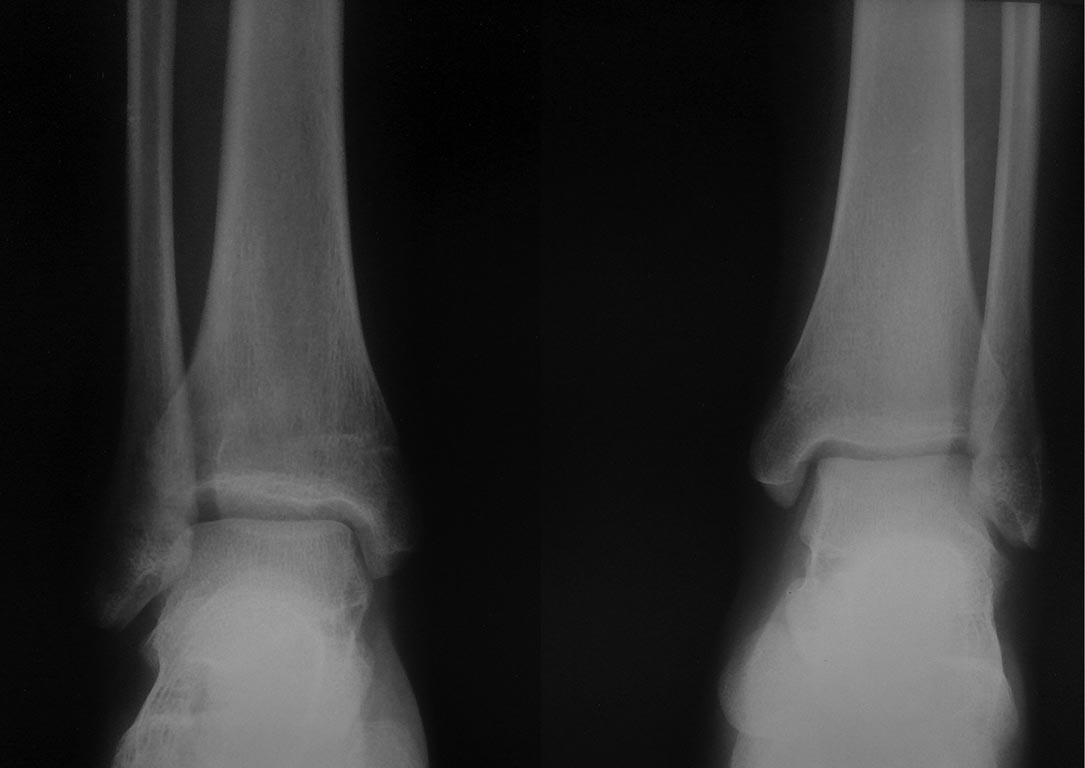

Последствия травмы голеностопного сустава у подростка

Хотим посоветоваться с Вами по тактике лечения девочки 13 лет.

К нам обратилась девочка с жалобами на боли в правом коленном суставе и стопе. Со слов боли в течение последних 6 месяцев, усиливаются после длительной ходьбы. В покое не беспокоят либо быстро купируются приемом НПВП. Ночных болей нет. По месту жительства выполнялись Р граммы коленных суставов и УЗИ. Какой либо существенной проблемы не обнаружено.

При осмотре походка не нарушена. Обращает на себя внимание, справа несколько больше контурируется головка правой малоберцовой кости. При пальпации болезненность в проекции, головки малоберцовой кости и малоберцового нерва. Боли в стопе в области пятки и тыла стопы. Пареза малоберцового нерва нет, парастезии, расстройств чувствительности нет. Невролог еще не смотрел. Других видимых и пальпируемых изменений не обнаружено. Единственное, что можно добавить, несколько увеличена латеральная лодыжка в сравнении с контралатеральной.

При измерении длины конечностей имеется укорочение правой голени до 1,5 см. При том сама пациентка этого не замечала. Каких либо беспокойств это укорочение доставляет. При «выпытывании» выяснили, что несколько лет назад был перелом голени в н/3, лечилась оперативно. Закрытая репозиция, остеосинтез спицами остеоэпифизиолиза большеберцовой кости в н/3 со смещением. Нашла выписку. В дальнейшем, каких либо жалоб нет. Пациентка была на амбулаторном приеме, успел сделать фото имеющихся снимков телефоном. Рентгенограммы какие есть. Извините.